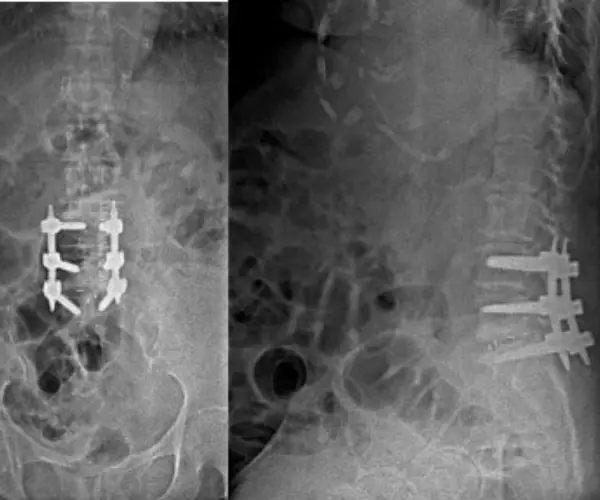

Lumbar Spine Solutions

Comprehensive care for lumbar disc herniations, stenosis, and spondylolisthesis with advanced fusion techniques like TLIF, ALIF, and OLIF.

Lumbar Spine

Comprehensive minimal access solutions for lower back conditions

Indications

- Herniated discs

- Spondylosis & Spondylolisthesis

- Tumours

- Stenosis

Procedures

- Micro Endoscopic Discectomy (MED)

- ALIF, TLIF, DLIF & OLIF

- Tubular Tumour Resection

- Tubular Lamino-Foraminotomy

- MIS Laminectomy